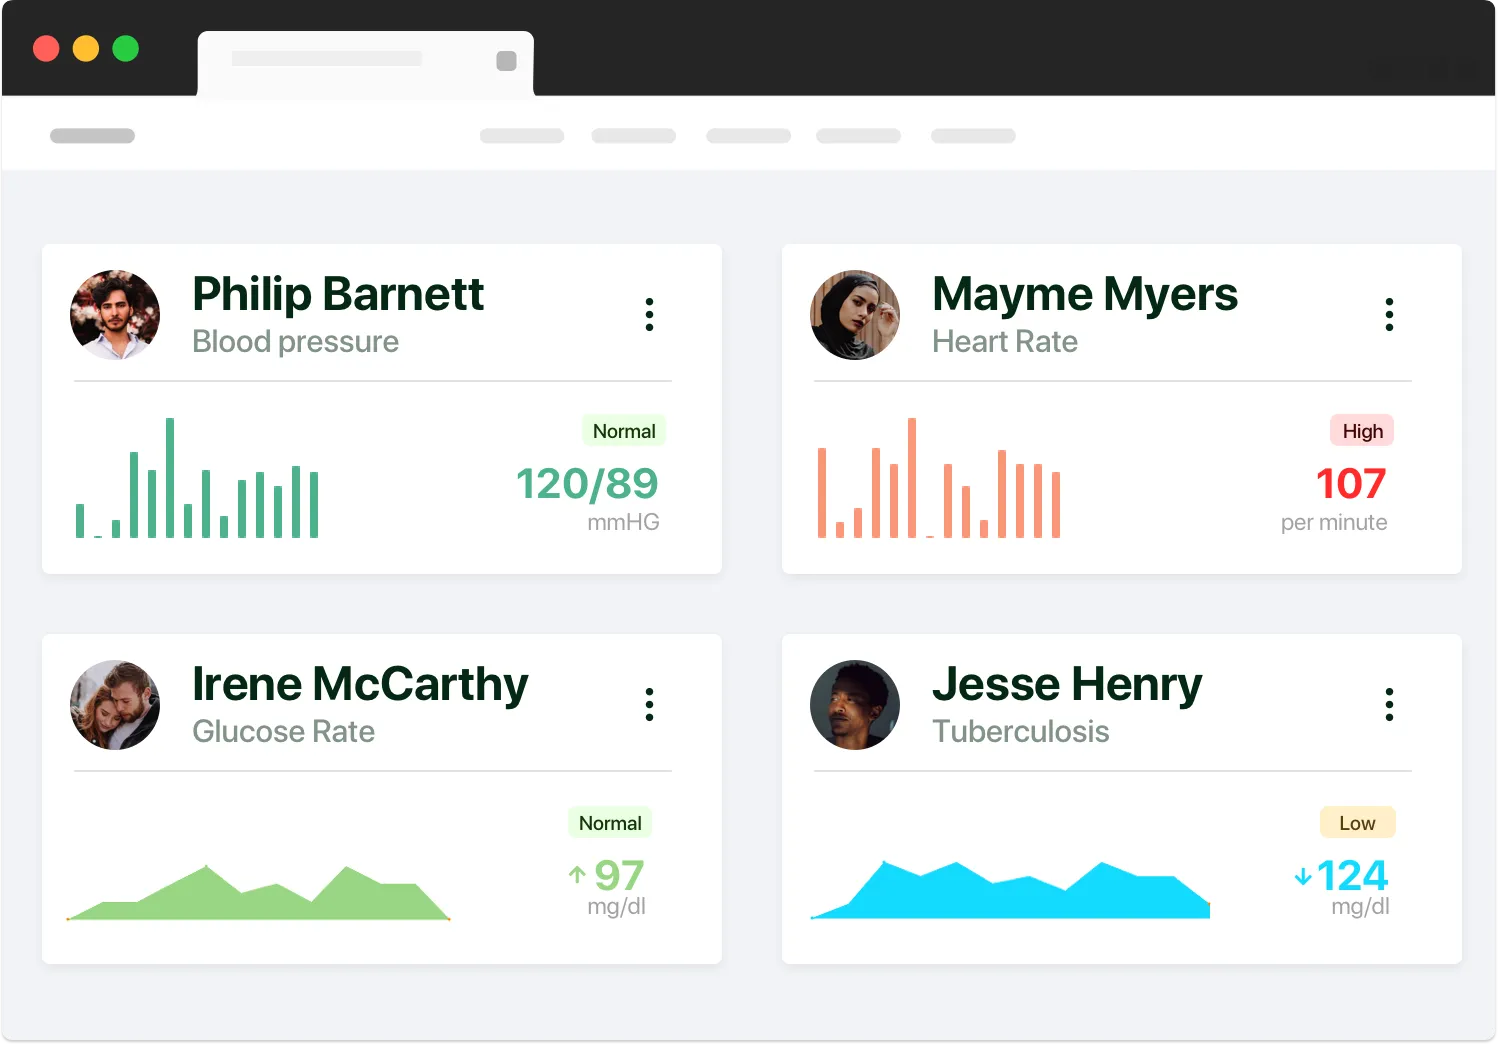

Performance Metrics: Track business performance, uptime, and user engagement.

Patient Analytics: Gain insights into patient demographics and behavior.

Real-time patient monitoring and data collection for proactive healthcare management.